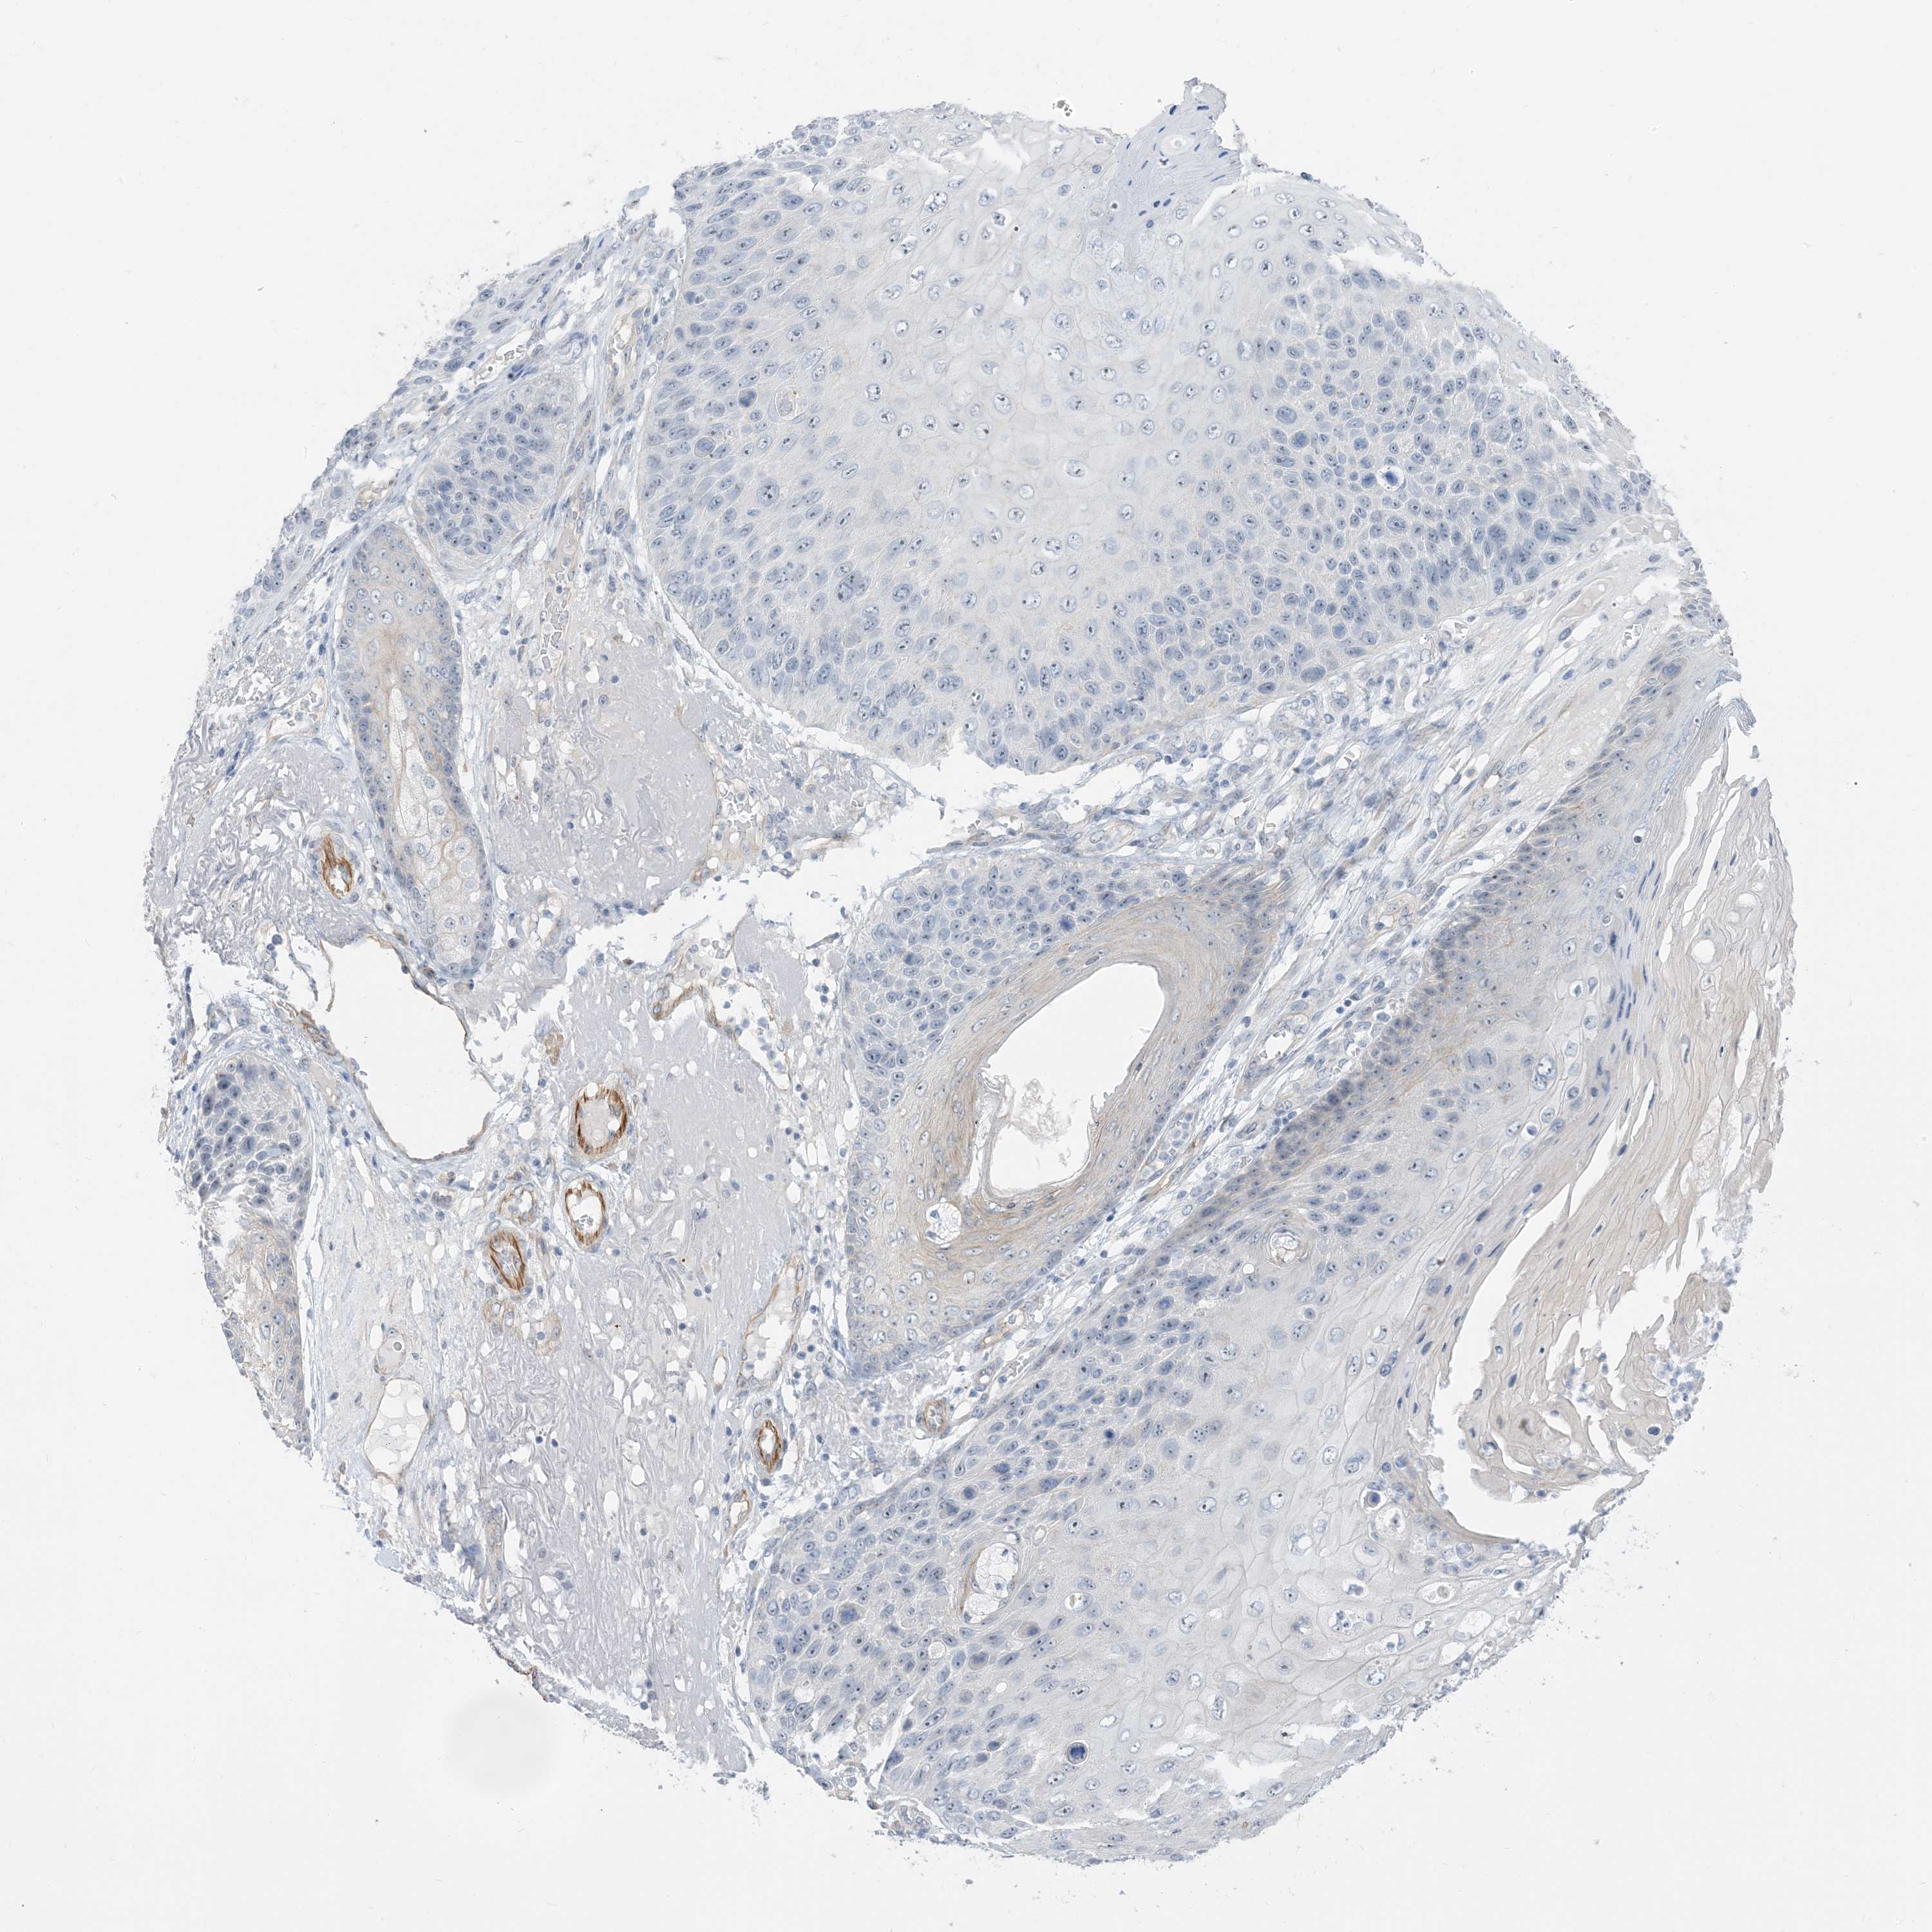

SKIN CANCER - Protein expressioni

A mouse-over function shows sample information and annotation data. Click on an image to view it in a full screen mode. Samples can be filtered based on level of antibody staining by selecting one or several of the following categories: high, medium, low and not detected. The assay and annotation is described here.

Each image is clickable and will lead to virtual microscopy that enables deeper exploration of all samples and also displays staining intensity scores, fraction scores and subcellular localization as well as patient and tissue information for each sample.

Antibody HPA035664

Staining

High

Medium

Low

Not detected

Intensity

Strong

Moderate

Weak

Negative

Quantity

>75%

75%-25%

<25%

None

Location

Nuclear

Cytoplasmic/membranous

Cytoplasmic/membranous,nuclear

Basal cell carcinoma